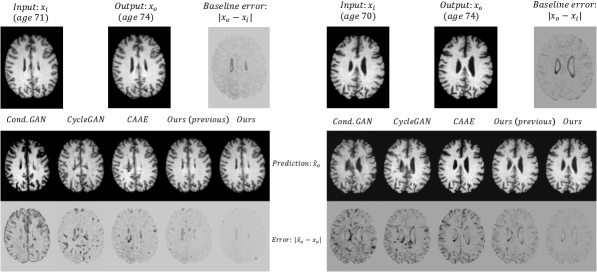

Refer to caption

Fig. 6: Example results of subjects with ground-truth follow-up studies. We predict output x^osubscript^𝑥𝑜\hat{x}_{o} from input xisubscript𝑥𝑖x_{i} using benchmarks and our method. We also show errors between the outputs and the ground-truths as |x^oxo|subscript^𝑥𝑜subscript𝑥𝑜|\hat{x}_{o}-x_{o}|. We can observe that our method achieves the most accurate results outperforming our previous method [65] and benchmarks. As a comparison, we also visualized the difference between inputs and ground-truth outputs as |xoxi|subscript𝑥𝑜subscript𝑥𝑖|x_{o}-x_{i}|. For more details see text.

Visual examples on two images from ADNI, are shown in Fig. 6. For both examples, our method generates most accurate predictions, followed by our previous method  [65], offering visual evidence to the observations above. The third best results are achieved by CAAE, where we can see more errors between prediction xo^^subscript𝑥𝑜\hat{x_{o}} and ground-truth xosubscript𝑥𝑜x_{o}. CycleGAN and Conditional GAN produced the poorest output images, with observable structural differences from ground-truth, indicating loss of subject identity. We can also observe that the brain ventricle is enlarged in our results and the difference between xisubscript𝑥𝑖x_{i} and xosubscript𝑥𝑜x_{o} is reduced, which is consistent with known knowledge that ventricle increases during ageing.